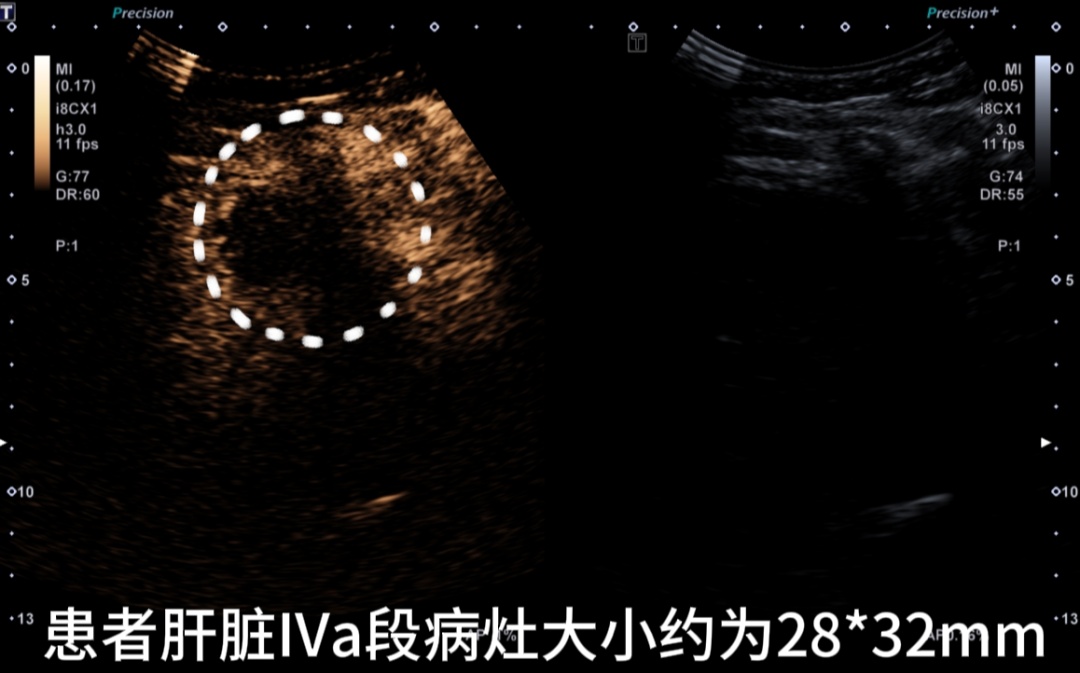

患者术前超声造影

IVb段病灶

IVa段病灶

两病灶内均无明显造影剂灌注,消融效果满意。